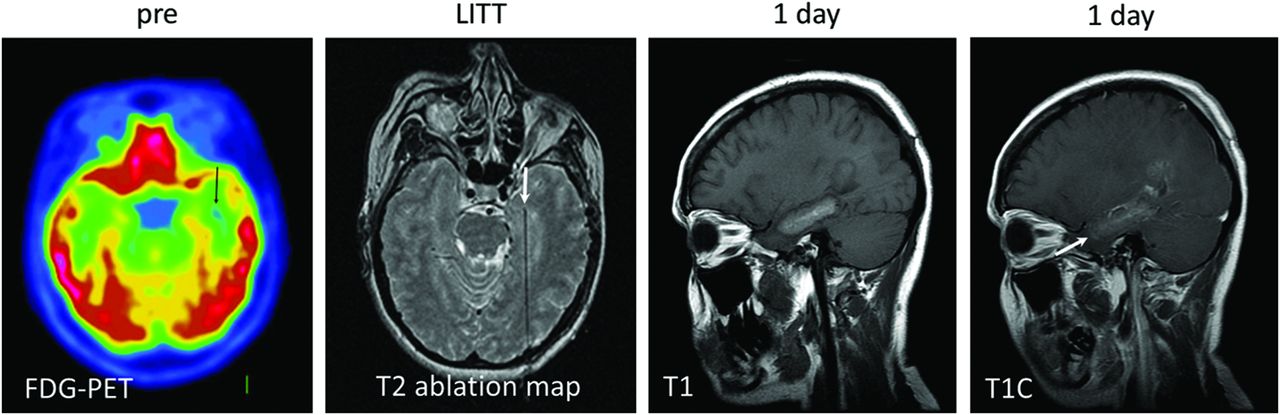

大約三分之一的癲癇依靠單純藥物治療不能得到控制。顳葉內(nèi)側(cè)癲癇(mesial temporal lobe epilepsy,MTLE)就是一類常見的難治性癲癇,需行手術(shù)治療。采用MRI監(jiān)測(cè)和調(diào)控下的激光間質(zhì)熱療(magnetic resonance-guided laser interstitial thermal therapy,MRg-LITT)毀損海馬杏仁核,是治療MTLE的新方法,它利用MRI引導(dǎo)和實(shí)時(shí)反饋消融癲癇病灶。

2017年一項(xiàng)對(duì)38例有難治性顳葉癲癇治療且無(wú)其他病變(包括腫瘤)的患者接受了MRI引導(dǎo)下的激光間質(zhì)熱療(LITT)治療的臨床研究結(jié)果顯示,18例(53%)發(fā)生了恩格爾I級(jí)結(jié)局,10例患者重復(fù)了手術(shù)/操作,發(fā)生了12例術(shù)后并發(fā)癥。隨訪時(shí)間為6到38.5個(gè)月。手術(shù)時(shí)間、住院時(shí)間與開顱手術(shù)相比有止痛要求。在MTLE定位良好的情況下,與傳統(tǒng)手術(shù)相比,此程序可提供相似(盡管稍低)的癲癇發(fā)作率。

MRI引導(dǎo)下的激光間質(zhì)熱療(LITT)可能是高危手術(shù)患者的替代治療選擇,更重要的是,它可能會(huì)增加難治性顳葉癲癇患者的手術(shù)咨詢。但是,數(shù)據(jù)有限,尚未評(píng)估長(zhǎng)期結(jié)果。需要進(jìn)一步研究以了解這種微創(chuàng)技術(shù)對(duì)難治性顳葉癲癇患者的潛力。